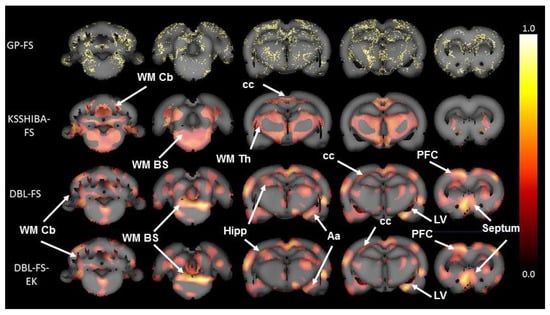

Figure 3 shows the brain areas selected by the methods with FS capabilities. As each voxel has an associated weight, the image masks represent the absolute value of these weight magnitudes for the selected of voxels as an indicator of the voxel relevance. In addition, since we have a model for each LOO iteration, Figure 3 displays the average values of these relevances (over all LOO iterations) and includes a normalization of their scales to the range ( 0 , 1 ) to simplify their analysis. As a result, we can observe that the GP-FS selected meaningless voxels in neurobiological terms while KSSHIBA detected well-defined areas corresponding to only WM tissues. Finally, the DBL-FS and DBL-FS+EK approaches obtained well-defined regions in the GM and WM tissues and the CSF, which are interpretable in neurobiological terms. Although both methods provided similar selections, DBL-FS+EK selected a reduced set of voxels.

Figure 3. Brain masks obtained by the FS of each model. Colors are defined in a linear scale and associated to the relevance of the voxel (white: more relevant; dark red: less relevant). GP-FS model yields meaningless results in neurobiological terms, where no anatomical regions can be identified. KSSHIBA-FS model only identifies brain areas related to WM deficits in schizophrenia. Both DBL-FS and DBL-FS+EK learn similar relevance in WM, GM, and CSF brain areas of interest in schizophrenia, such as the hippocampus (hipp), prefrontal cortex (PFC), amygdala (Aa), septum, lateral ventricles (LV), corpus callosum (cc), WM cerebellar (WM Cb), and WM brainstem (WM BS) fibers.

Analyzing in detail the regions selected by the DBL-FS and DBL-FS+Ek models, we can verify that these areas belong to brain regions whose morphometric changes have been related to schizophrenia, based on the literature. First, as for CSF, the areas with the greatest weight were the most frontal areas of the lateral ventricles and the third ventricle. One of the morphometric hallmarks in schizophrenia is the enlargement of the ventricles [23,40], which is consistent with the learned selection. Second, regarding GM, our model clearly defined anatomical areas, such as the prefrontal cortex (PFC), hippocampus, amygdala, and septum, some of them in both hemispheres. Numerous studies have demonstrated the relevance of the morphological changes of these areas in mental disorders [41,42] together with the disconnection and lack of symmetry between both cerebral hemispheres [43,44]. Similar volumetric abnormalities have also been reported for the animal model used in this study [24,45]. In addition, the method also detected the medial septum, which plays a significant role in dopamine-related disorders such as schizophrenia [46,47] and addictions [48,49,50], which highlights the relevance of this structure in mental disorders. Regarding WM, the method found three well-defined brain areas, the frontal part of corpus callosum and WM tracts of the brainstem and the cerebellum [51,52].

Regarding the inclusion of expert knowledge by means of the α prior, it reveals two interesting behaviors. First, it demonstrates the robustness and potential of the standard DBL-FS since it is able to obtain similar accuracy and roughly similar brain masks to its DBL-FS+EK extension without the need for expert information. Second, the possibility of including expert knowledge makes the model converge faster, and it also refines the brain region selection. It is important to note that, although the expert knowledge guides the inference process, the model is also learning from the data, allowing it to redefine the initial expert knowledge into a specific set of voxels. For instance, looking at Figure 3, we can see that using expert knowledge, we obtain a higher relevance associated with the core of the WM brainstem and hippocampal areas.